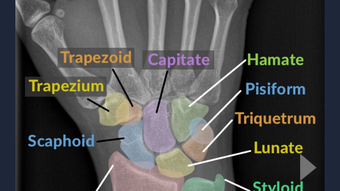

Sublux is a medical image app that aims to improve the experience of radiology as a diagnostic tool by making it more accessible to medical providers.

With Sublux, you can easily and intuitively diagnose many common medical conditions, from simple broken bones to severe illnesses and even cancer.

The app includes hundreds of different radiology findings, along with their corresponding diagnoses and clinical pearls and insights.